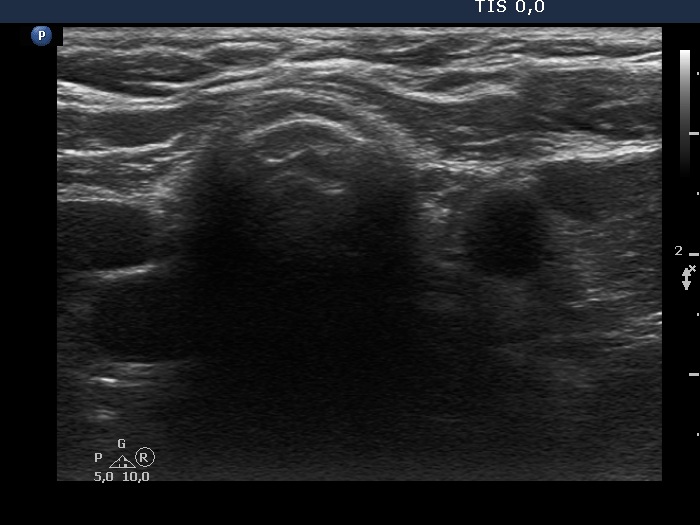

Ultrasonography. There was no thyroid tissue in the thyroid beds. The transverse view of the left lobe was deceptive because the muscle fiber on this scan mimicked thyroid remnant. Longitudinal section was decisive.

Comment. As in many cases, the longitudinal scan is more informative than the transverse view regarding the judgement of a discrete mass.